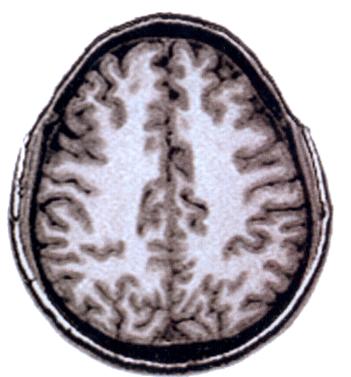

Méthodes d'étude du cerveau

Images Méthodes Etudes Cerveau

cerveauIRM.JPG